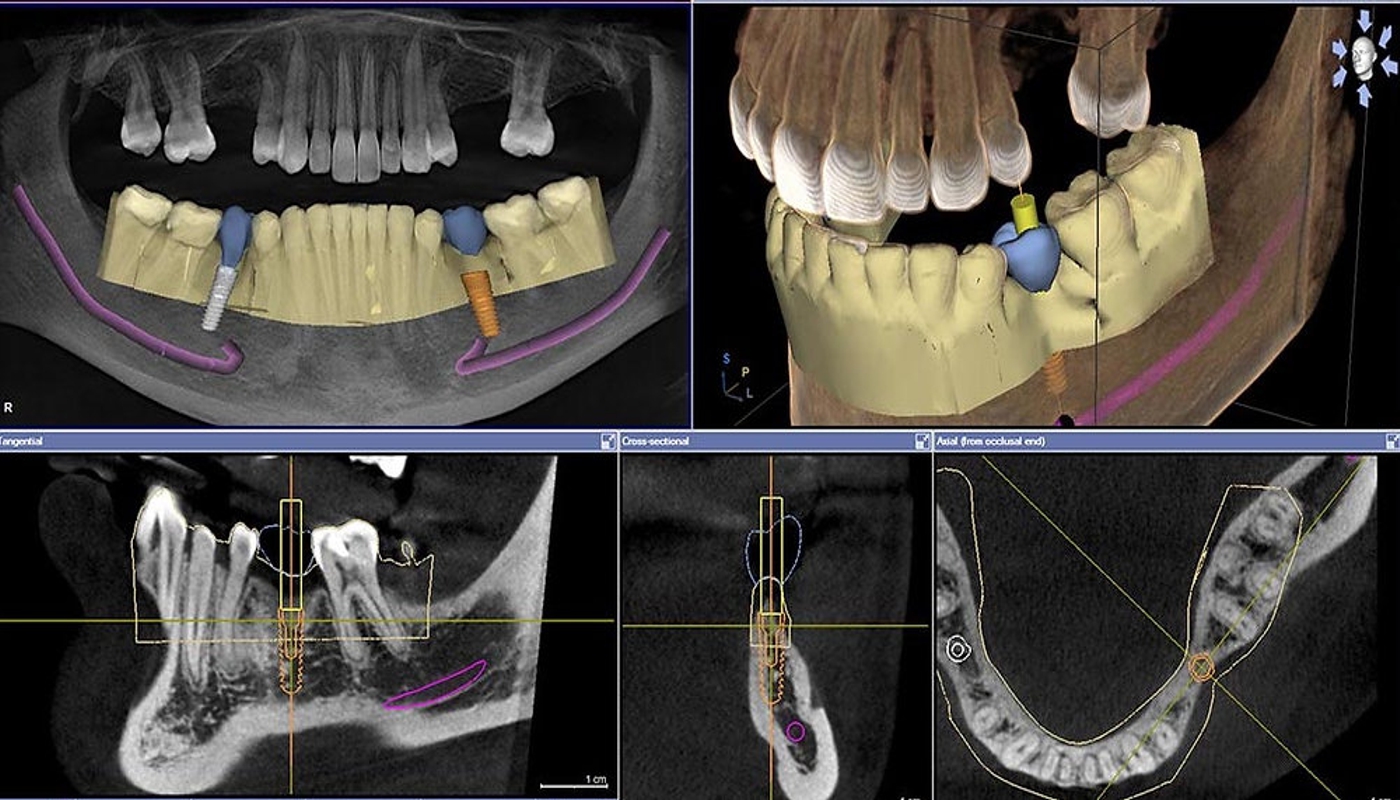

Presso lo Studio Kol adottiamo un approccio avanzato e personalizzato per l’implantologia, utilizzando tecnologie di ultima generazione come la TAC Cone Beam e lo scanner intraorale, che consentono una diagnosi digitale e una pianificazione chirurgica estremamente precisa. L’inserimento degli impianti avviene mediante chirurgia guidata, riducendo così al minimo il trauma ai tessuti circostanti. Dopo pochi mesi, grazie al processo di osteointegrazione, l’impianto si fonde saldamente con l’osso, permettendo l’applicazione della protesi definitiva in ceramica, che garantisce risultati estetici e funzionali ottimali.

Le tecnologie avanzate di cui disponiamo includono la chirurgia guidata digitale per un posizionamento sicuro, l’utilizzo di stampanti 3D per realizzare guide chirurgiche e protesi personalizzate, nonché strumenti sofisticati come il bisturi piezoelettrico e il motore chirurgico implantare per interventi minimamente invasivi.